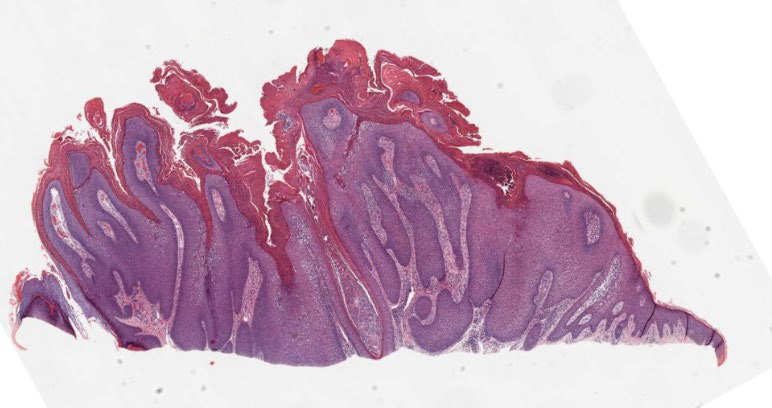

I am a great mimic of basal cell carcinoma. I am a hair follicle tumor. I am seen generally on the face, and some versions of me, I look like a paisley tie. Who am I? 🤔 #pathx #dermpath #fammed #medx #pathtwitter #path4people #pathagonia

Path4People's tweet image. I am a great mimic of basal cell carcinoma.

I am a hair follicle tumor.

I am seen generally on the face, and some versions of me, I look like a paisley tie.

Who am I? 🤔